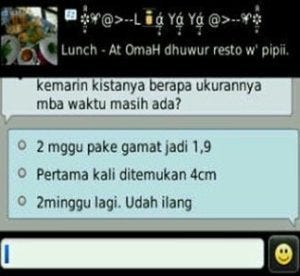

Testimoni | Dr Suryo, SpOG - Kesehatan Reproduksi

Testimoni | Dr Suryo, SpOG - Kesehatan Reproduksi

Kista 12 cm 3 tahun nikah hamil pertama | Dr Suryo, SpOG - Kesehatan Reproduksi

Kista 12 cm 3 tahun nikah hamil pertama | Dr Suryo, SpOG - Kesehatan Reproduksi

Testimoni | Dr Suryo, SpOG - Kesehatan Reproduksi

Testimoni | Dr Suryo, SpOG - Kesehatan Reproduksi

Babyprogram berhasil hamil dengan kista coklat hampir 5 cm | Dr Suryo, SpOG - Kesehatan Reproduksi

Babyprogram berhasil hamil dengan kista coklat hampir 5 cm | Dr Suryo, SpOG - Kesehatan Reproduksi